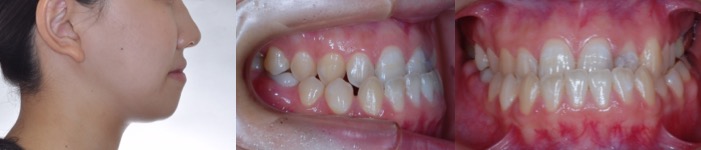

術前矯正治療開始時 21歳6カ月